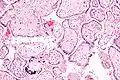

![]()

Numerous pathologies can affect the placenta.

Micrograph of CMV placentitis.